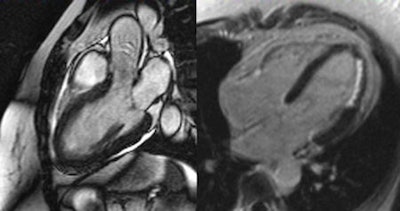

Takotsubo cardiomyopathy, also known as transient apical ballooning syndrome or stress cardiomyopathy. General MRI features include regional ventricular ballooning (apical, as in this case, and sometimes midventricular or basal), reduction of left ventricular ejection fraction, myocardial edema corresponding to regional wall motion abnormality (not shown), and absence of significant fibrosis/necrosis on late enhancement imaging (not shown)."Cardiac MRI permits high diagnostic confidence," Emrich summarized. "As a result of our study, we recommend that for all cases of nondescript chest pain with accompanying lab results hinting towards a myocardial infarction and with inconspicuous catheterization, cardiac MRI should be used. Patients will profit from a correct diagnosis and suitable subsequent therapy."